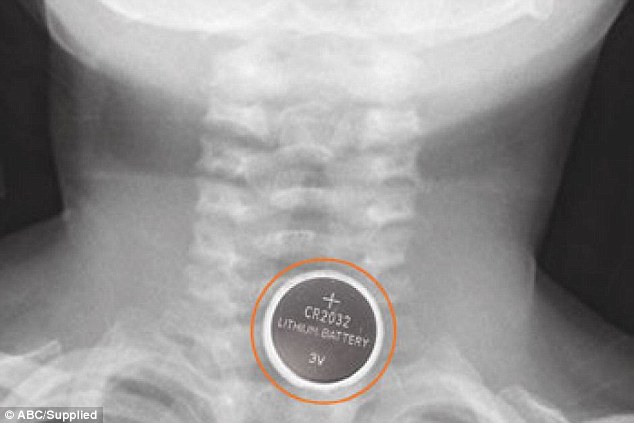

Их Британи улсад тоглоомонд байдаг товчин баттерейг залгиснаас болж хоёр хүүхэд амиа алдаж, таван хүүхэд насан туршийн согогтой болсон хэрэг өнгөрөгч онд гарсан. Үүнтэй холбогдуулан тус улсаас иргэдийнхээ сонор сэрэмжийг нэмэгдүүлэх зорилгоор шат дараатай арга хэмжээ зохион байгуулж байгаагийн нэг нь баттерей залгисны дараа ямар зүйл болдгийг харуулсан зурагт хуудас болоод бичлэг юм. Үүнийгээ Британийн эмч нар зайдсан дээр жишээ болгон харуулжээ. Товчин баттерей хүүхдийн хоолойд тээглэсэн бол хоёр цагийн дотор л цус алдалтад хүргэдэг байна.

Манай улсын иргэдийн дунд ч товчин баттерейг хүүхдийнхээ тоглоомноос салгаж авах, холдуулах арга хэмжээг өрнүүлэх ёстой гэж цахим ертөнцөөр шуугиж байгаа юм. Иргэн та хүүхдийнхээ тоглоомонд яг үүнтэй ижил товчин баттерейгаар ажилладаг хичнээн тоглоом байгааг олж, баттерейг нь салгаж аваарай.